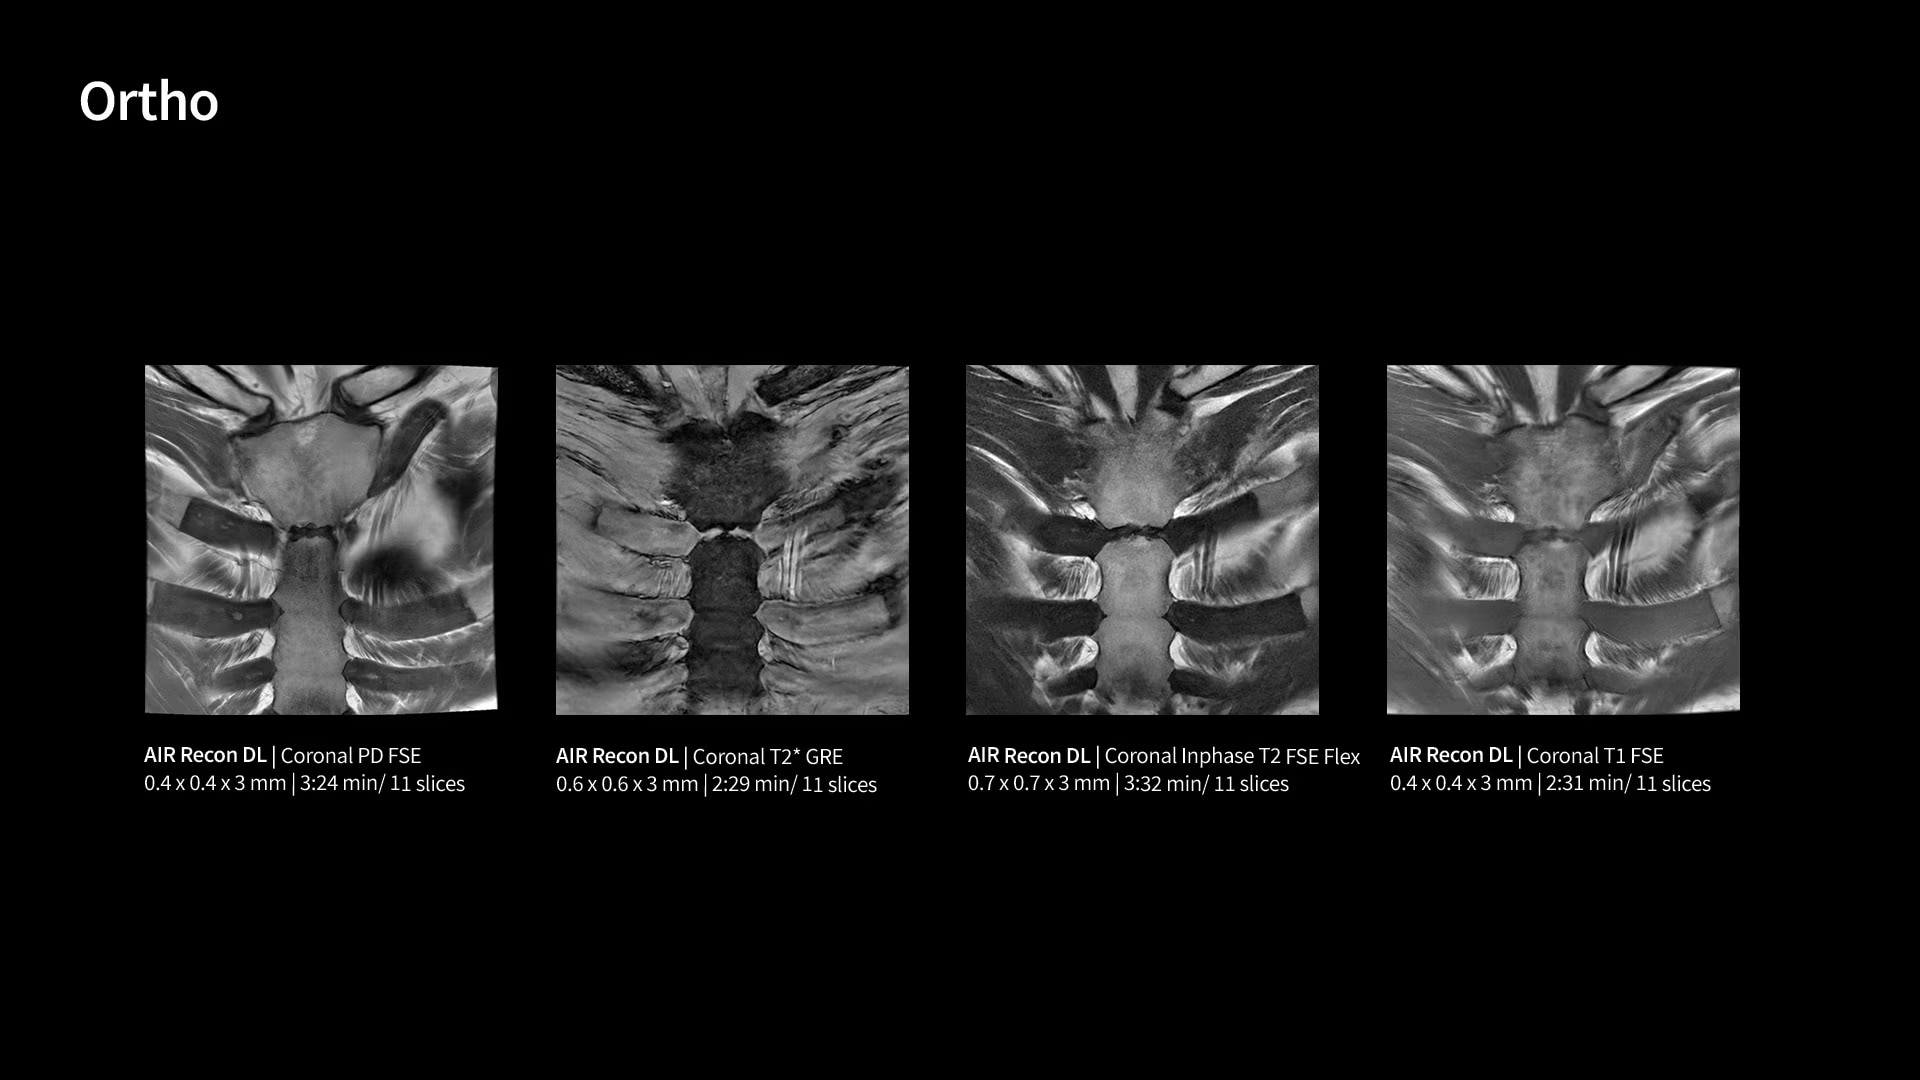

Unlock your potential

With GE HealthCare's comprehensive suite of deep-learning solutions integrated into SIGNA Sprint, you can unlock the full potential of your MRI system. No need for complicated patient setups or imaging protocols. The exceptional intelligence of our AI solutions offer multiple benefits, with AIR Recon DL giving pin-sharp images, Sonic DL accelerating scans up to 12x, and AIR x enabling automated slice placement. All helping to enhance your department’s workflow efficiency, increase patient throughput, and get the diagnostic clarity you need, faster.¹ Meaning you can spend more time on what truly matters—personalized patient care, enabling optimized treatment plans and treatment response monitoring—ultimately, supporting better clinical outcomes.